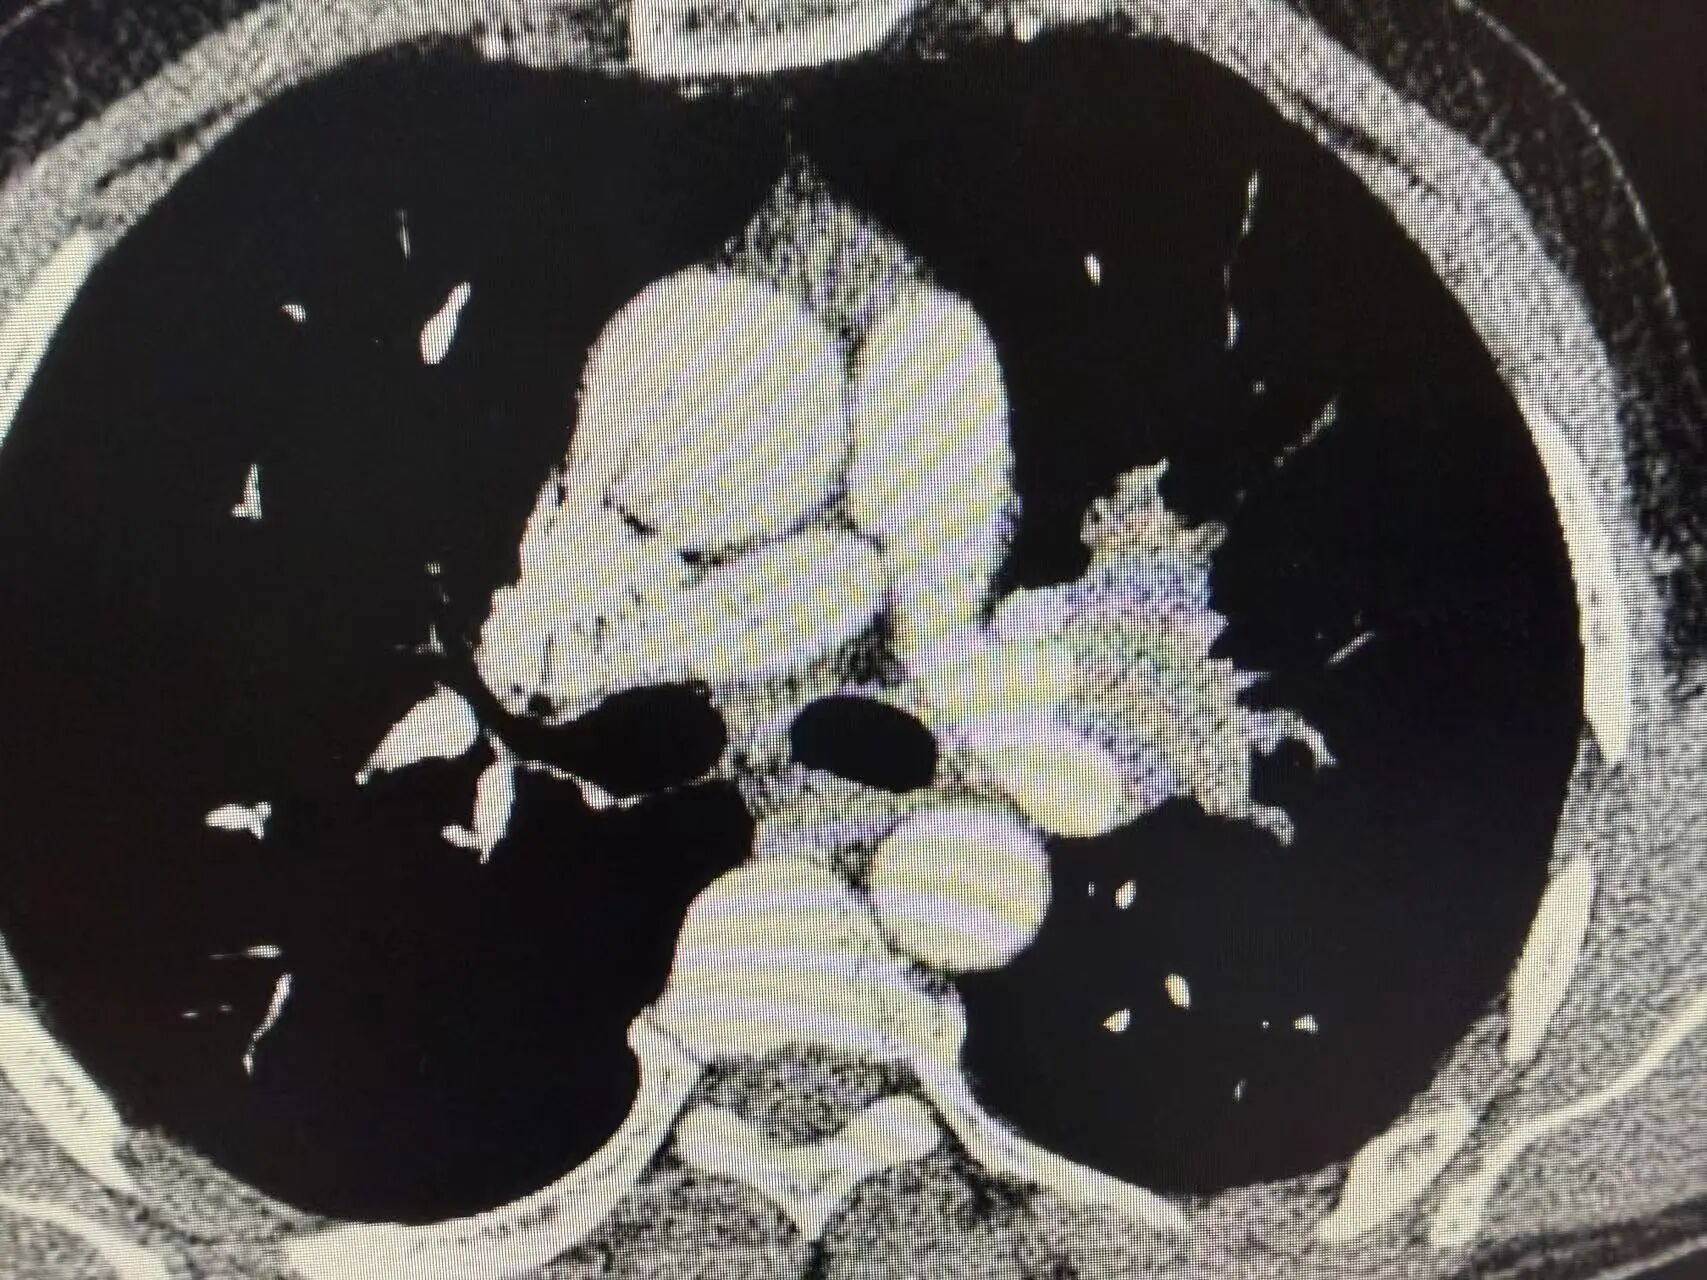

几个周期的治疗结束后,复查CT的结果传来了好消息:肿瘤明显缩小,原本粘连的血管也逐渐松动!这意味着,王叔终于获得了宝贵的手术机会,曾经的“不可切”,如今变成了“可切”。

新辅助治疗前CT:可见左上肺中央型占位,肿瘤侵犯血管